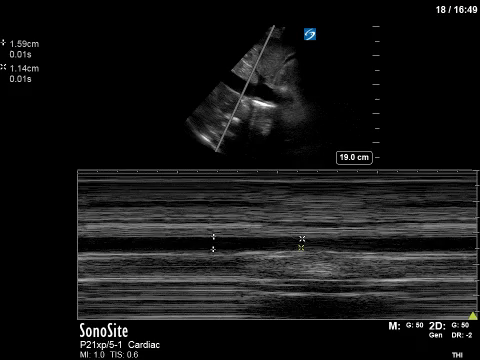

- Dùng đầu dò cong lớn(convex) hoặc đầu dò siêu âm tim(phased array), đặt đầu dò theo mặt cắt dọc vị trí dưới mũi ức lệch qua bên mạng sườn phải 1-2 cm → lách đầu dò để tìm IVC. Mặt cắt chuẩn sẽ cho IVC có đường kính lớn nhất, thấy được tĩnh mạch gan đổ vào IVC và IVC đổ vào nhĩ phải.

- Dùng M mode cắt trên IVC đo từ bờ nhĩ phải ra 3cm: đo sự thay đổi đường kính IVC theo chu kì hô hấp.

- Tính chỉ số xẹp IVC (IVC Collapsibility Index) ở bệnh nhân thở tự nhiên và chỉ số dãn IVC (IVC Distensibility Index) ở bệnh nhân thở máy áp lực dương.